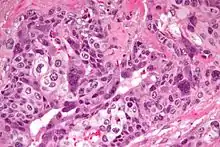

| Micrograph of choriocarcinoma showing both of the components necessary for the diagnosis - cytotrophoblasts and syncytiotrophoblasts. The syncytiotrophoblasts are multinucleated and have a dark staining cytoplasm. The cytotrophoblasts are mononuclear and have a pale staining cytoplasm. H&E stain. | |

Characteristic feature is the identification of intimately related syncytiotrophoblasts and cytotrophoblasts without formation of definite placental type villi. Since choriocarcinomas include syncytiotrophoblasts (beta-HCG producing cells), they cause elevated blood levels of beta-human chorionic gonadotropin.

Syncytiotrophoblasts are large multi-nucleated cells with eosinophilic cytoplasm. They often surround the cytotrophoblasts, reminiscent of their normal anatomical relationship in chorionic villi. Cytotrophoblasts are polyhedral, mononuclear cells with hyperchromatic nuclei and a clear or pale cytoplasm. Extensive hemorrhage is a common finding.